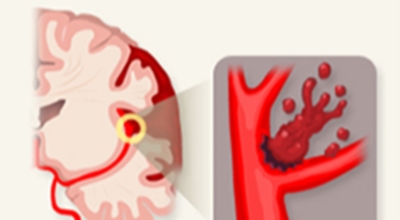

뇌졸중은 뇌경색과 뇌출혈 두가지로 나뉘게 돼요. 먼저 뇌경색은 뇌혈관이 막혀 영양분과 산소를 제공하는 피가 통하지 않는 상태로 원은은 크게 세 가지로 나눌 수 있는데요 동맥경화증이 생겨 좁아진 부위로 인하여 혈액공급이 부족해지거나 좁아지다가 결국 막혀버리는 경우, 큰 혈관에서 분지한 작은 혈관들이 고혈압 등으로 압박을 받으면 혈관이 막히는 경우가 있어요.

또한 심장 판막질환이나 심방세동 또는 심근병 등과 같은 심장 질환이 있는 경우 심장에서 혈전이 만들어지고 그게 뇌로 흘러가게 되면 뇌혈관을 막게 되는 경우가 있어요. 뇌출혈은 뇌경색과 반대로 뇌혈관이 터져서 생기는 뇌내 출혈과 거미막하 출혈로 나누게 돼요. 거미막하출혈은 혈관벽의 약한 부분이 부풀어 오르는 뇌동맥류가 터지는 경우와 관련성이 크다고 해요.